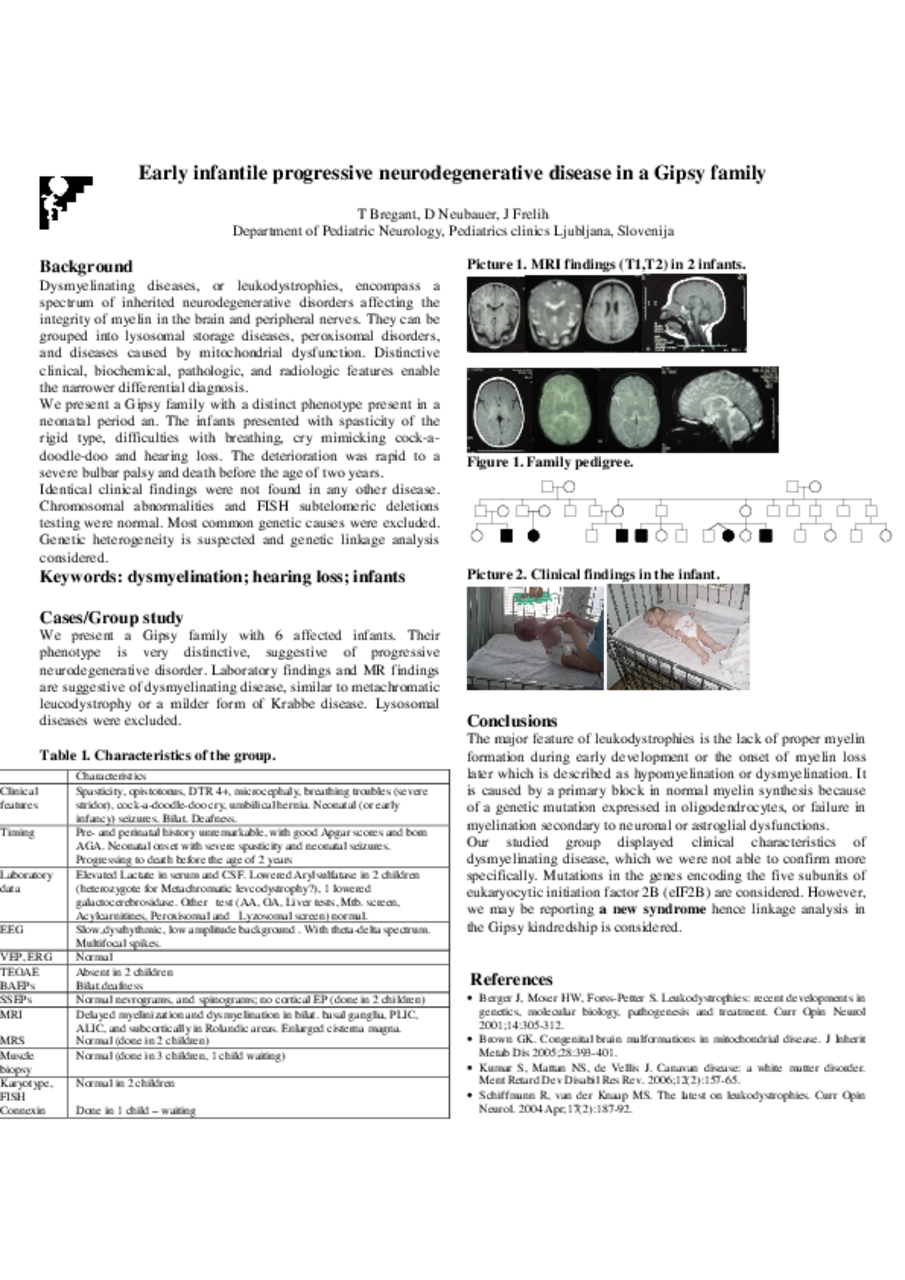

Background: Dysmyelinating diseases, or leukodystrophies, encompass a spectrum of inherited neurodegenerative disorders affecting the integrity of myelin in the brain and peripheral nerves. They can be grouped into lysosomal storage diseases, peroxisomal disorders, and diseases caused by mitochondrial dysfunction. Distinctive clinical, biochemical, pathologic, and radiologic features enable the narrower differential diagnosis. We present a Gipsy family with a distinct phenotype present in a neonatal period an. The infants presented with spasticity of the rigid type, difficulties with breathing, cry mimicking cock-a-doodle-doo and hearing loss. The deterioration was rapid to a severe bulbar palsy and death before the age of two years. Identical clinical findings were not found in any other disease. Chromosomal abnormalities and FISH subtelomeric deletions testing were normal. Most common genetic causes were excluded. Genetic heterogeneity is suspected and genetic linkage analysis considered. Cases/Group study: We present a Gipsy family with 6 affected infants. Their phenotype is very distinctive, suggestive of progressive neurodegenerative disorder. Laboratory findings and MR findings are suggestive of dysmyelinating disease, similar to metachromatic leucodystrophy or a milder form of Krabbe disease. Lysosomal diseases were excluded. Characteristics of infants encompass clinical features: spasticity, opistotonus, microcephaly, breathing troubles with a severe stridor and a distinctive cock-a-doodle-doo cry, some have umbilical hernia. They have early infancy seizures and bilat. deafness.their pre- and perinatal history was unremarkable, with good Apgar scores and born AGA. Neonatal onset is profound with severe spasticity and neonatal seizures, progressing to death before the age of 2 years Conclusions: The major feature of leukodystrophies is the lack of proper myelin formation during early development or the onset of myelin loss later which is described as hypomyelination or dysmyelination. It is caused by a primary block in normal myelin synthesis because of a genetic mutation expressed in oligodendrocytes, or failure in myelination secondary to neuronal or astroglial dysfunctions. Our studied group displayed clinical characteristics of dysmyelinating disease, which we were not able to confirm more specifically. Mutations in the genes encoding the five subunits of eukaryocytic initiation factor 2B (eIF2B) are considered. However, we may be reporting a new syndrome hence linkage analysis in the Gipsy kindredship is considered.